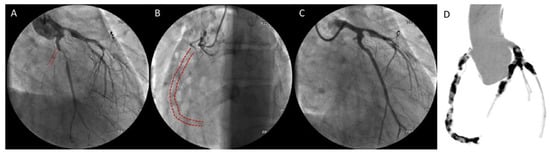

Polyarteritis nodosa is a systemic necrotizing vasculitis which predominantly involves medium-sized arteries, more rarely small muscular arteries in middle-aged adults. Unlike microscopic polyarteritis, granulomatosis with polyangiitis, polyarteritis nodosa is antineutrophil cytoplasmic antibodies (ANCA)-negative []. It may affect virtually any organ in the body (kidneys, skin, joints, muscles, nerves, and gastrointestinal tract), usually in combination, but usually does not involve the lungs. Coronary involvement is considered to be rare but may be severe, including aggressive three-vessel disease with infaust outcome (Figure 1) []. Clinical sequelae of this involvement include congestive heart failure, hypertension, pericarditis, and arrhythmias.

Figure 1.

Coronary angiography (A–C) and computed tomography image (D) of three-vessel disease in a 22-years old patient with polyarteritis nodosa. Angiography showed chronic total occlusion of the right and circumflex coronaries. Reproduced with permission from [] under the creative common license (http://creativecommons.org/publicdomain/zero/1.0/) (accessed on 3 March 2021).